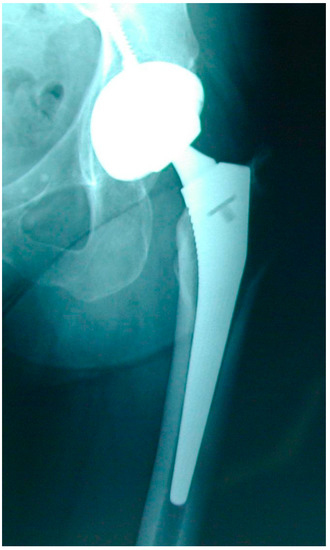

Early HRA failure modes mainly consisted of femoral neck fractures [11] (Figure 2), treated by revising only the femoral component and preserving the acetabular component and the MoM bearing. Large diameter MoM femoral heads modularly fitting on a prosthetic femoral stem had been specifically designed for these femoral component-only revisions of HRA (Figure 3). Following the good initial results of the Metasul® MoM hips and the reduced risk of dislocation with large diameter femoral heads, these HRA revision big femoral head (BFH) components were also used for primary THA, despite the smaller coverage angle of the acetabular design, the introduction of an additional MoM articulation at the taper–trunnion head–neck junction and despite the fact that these components had not been thoroughly tested for this indication [12,13].

Figure 2.

Early failure of an MoM HRA due to femoral neck fracture.

Figure 3.

MoM total hip arthroplasty with large diameter femoral head.